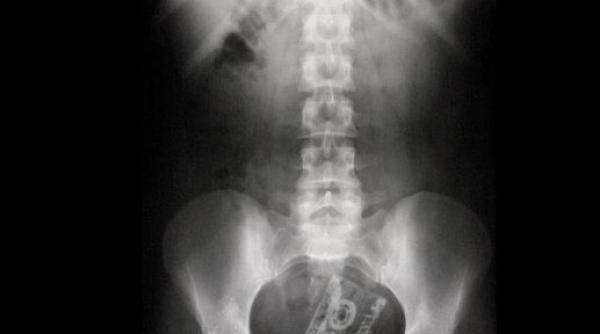

Medicii din California, în stare de ŞOC! Ce au găsit specialiştii în intestinul gros al unui bărbat întrece orice imaginaţie